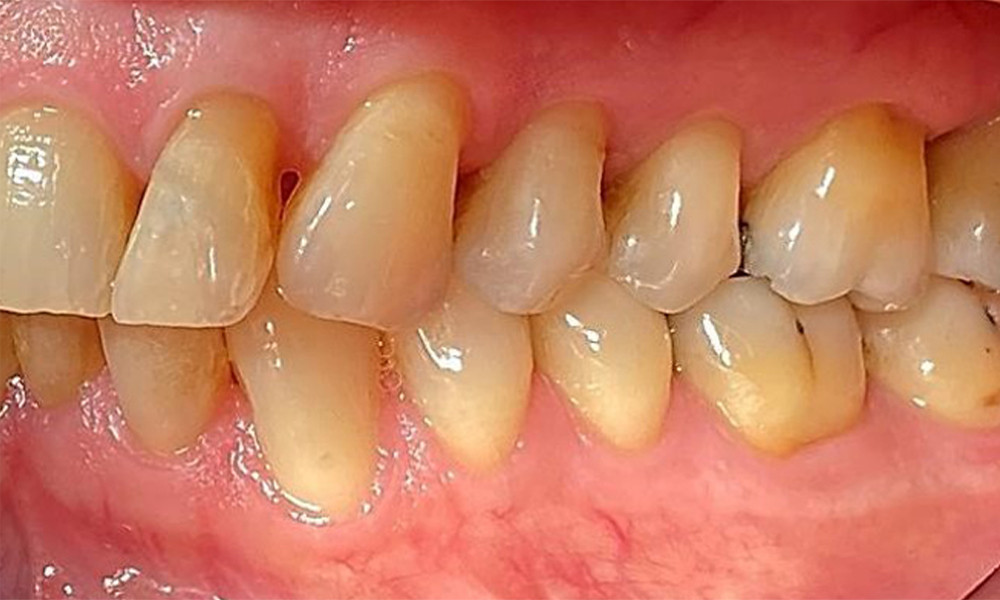

Left lateral view including the recessions.

Fig. 4 Left lateral view including the recessions. © Dr R. Krapf

The patient has a full dentition with 28 teeth, which includes amalgam and composite fillings in the molar and premolar regions. There is a visible clinical marginal gap present on tooth 14. Tooth 27 has an adequate gold inlay. There are also generalized attritions and abrasions. (Fig. 2, Fig. 3, Fig. 4, Fig. 5, Fig. 6)

Periodontal findings

The patient has stage II, grade B periodontitis (5). At 1 to 3 mm, the clinical probing depths were within the physiological range. Localized probing depths of 5 mm were observed on the mesiopalatal aspects on both 17 and 27. There are generalized recessions of 1–3 mm with partial loss of the interdental papillae (Fig. 2, Fig. 3, Fig. 4)